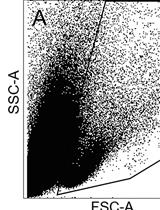

MHC class I molecules present peptides to cytotoxic T cells allowing the immune system to scan for intracellular pathogens and mutated proteins. The generation of antigenic peptides is a multistep process that ends in the endoplasmic reticulum (ER). Only peptides with the right length and sequence will bind nascent MHC class I molecules in the ER. This protocol allows for detachment of the endogenous peptides bound to MHC class I molecules by preserving them for the binding of high affinity synthetic peptides. The complete dissociation of endogenous peptides by mild acid treatment as well as the binding of synthetic peptides to MHC class I molecules will be evaluated measuring HLA class I molecules express on the cell surface by flow cytometry. The mouse antibody W6/32 which recognizes β2m associated HLA-A, -B, -C, -E and -G heavy chains is suitable for this propose. Any tumor cell line that expresses surface HLA class I molecules is suitable for the assay. Another important aspect is to know the HLA class I typing of tumor cell line to allow selection of the known high affinity peptides.